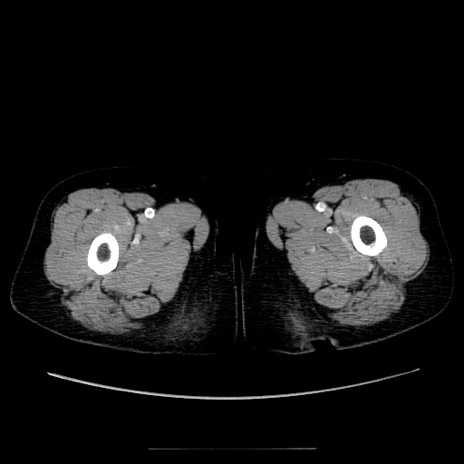

症例5(横断像)

【症例】70歳代女性

【主訴】お腹が張る

【現病歴】1週間くらい前から腹部膨満の自覚あり。昨日夜から増悪したため、本日救急外来受診。

【身体所見】意識清明、BT 36.5℃、BP 165/106mmHg、HR 80bpm、SpO2 98%、腹部:膨満、軟、自発痛・圧痛なし、触診にて不快感あり、腸蠕動音:減弱

【データ】WBC 12600、CRP 1.04